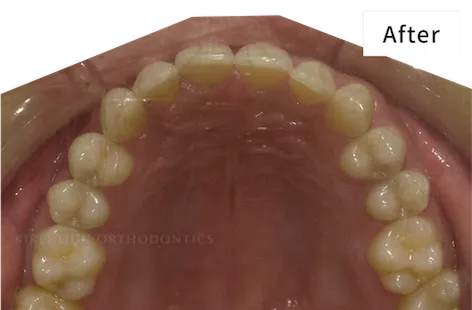

治療期間 約6カ月

プラン ライトプラン(14枚コース)

治療費44万円(税込)